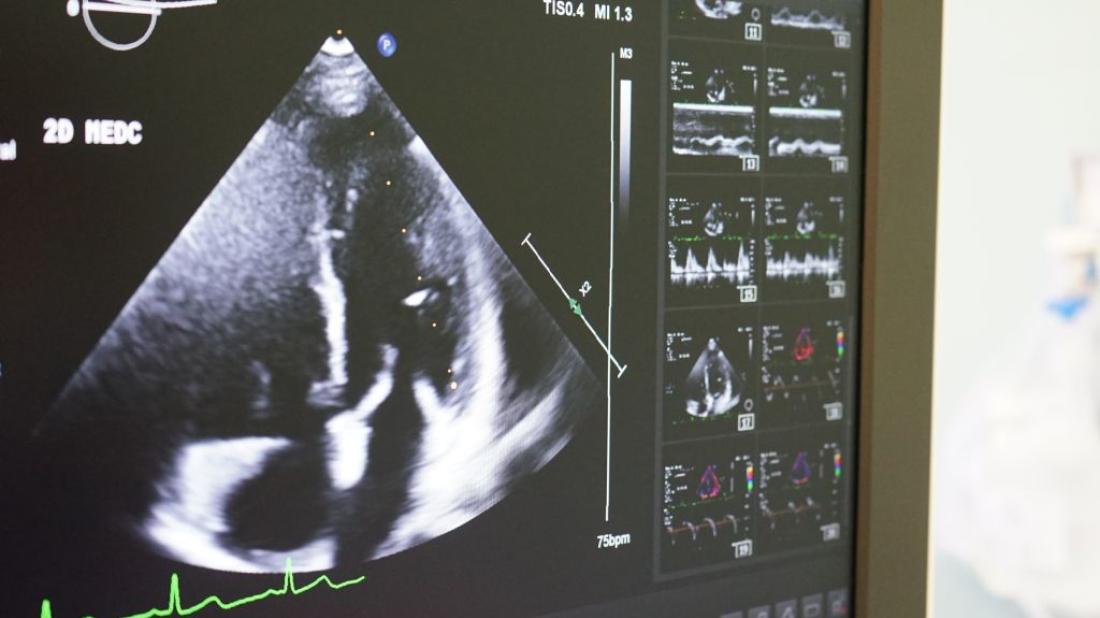

Диагноз ДМПП сердца у детей обычно устанавливается с помощью эхокардиографии, которая позволяет визуализировать структуру сердца и определить размер и расположение дефекта. В некоторых случаях может потребоваться трансторакальная или трансэзофагеальная эхокардиография для более точной оценки состояния сердца. Это важный шаг, который помогает врачам разработать оптимальный план лечения.